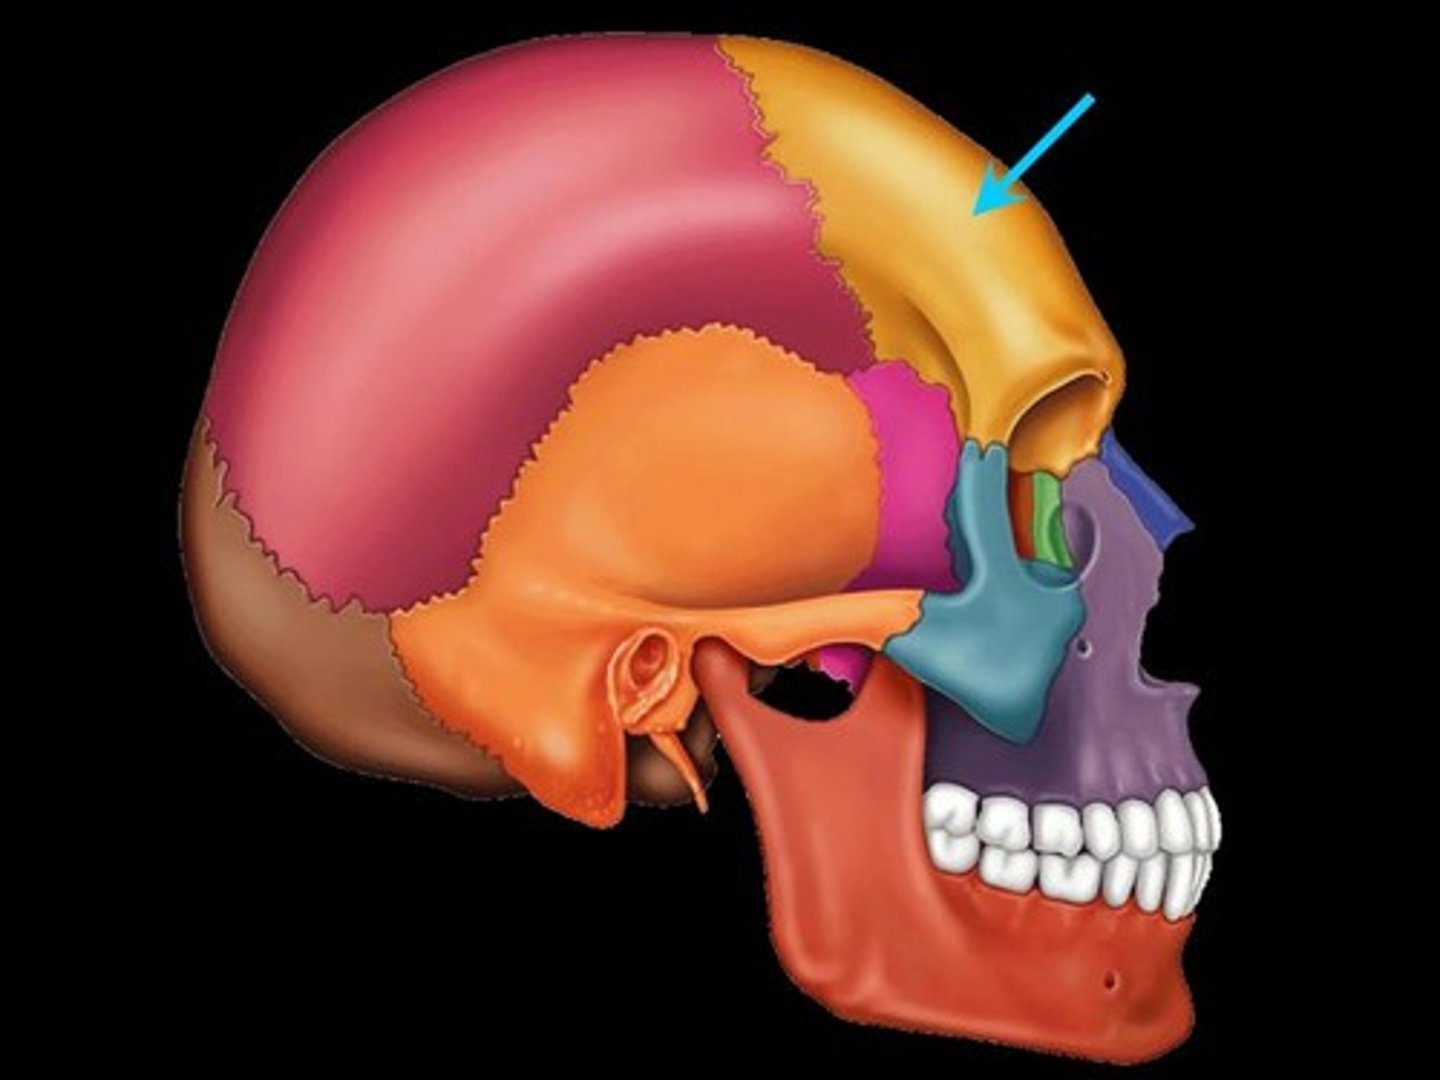

Frontal Bone

the large cranial bone forming the front part of the cranium: the forehead and the upper part of the orbits